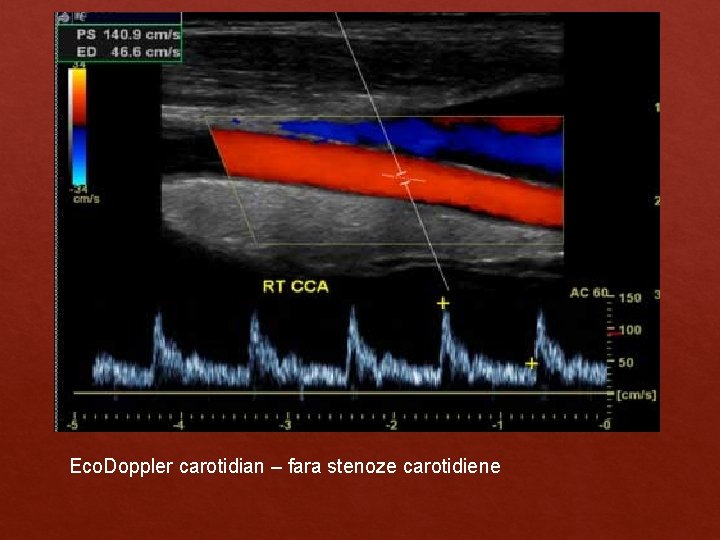

Eco. Doppler carotidian – fara stenoze carotidiene